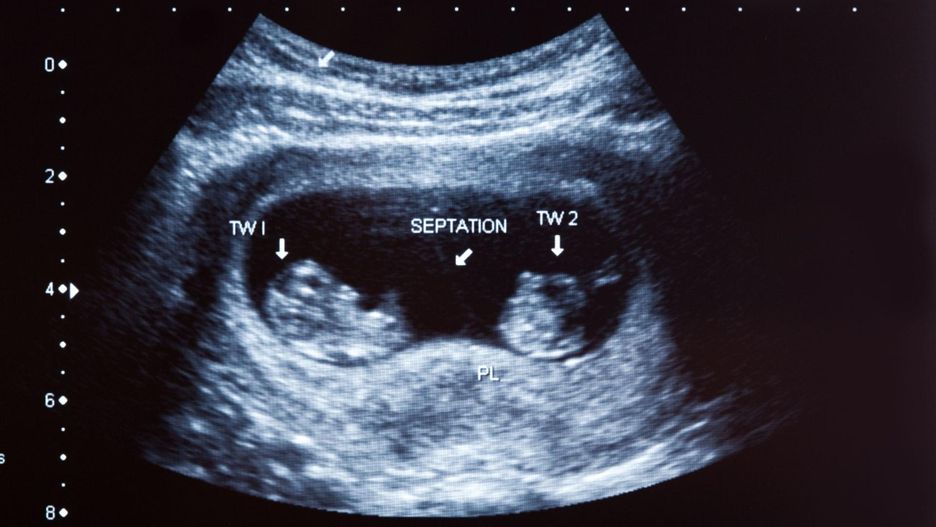

Kobieta zgłosiła się do szpitala z dolegliwościami związanymi z niedawnym upadkiem. Nie było w tym nic zaskakującego, podjęto więc standardowe procedury. Lekarz zlecił wykonanie badania rentgenowskiego. Zdjęcie, które otrzymano po badaniu, wprowadziło lekarzy w osłupienie.

Okazało się, że w jamie brzusznej starszej kobiety znajduje się obumarły płód. Był on duży i zwapniony. Lekarze oceniają, że znajdował się w organizmie matki około 50 lat.